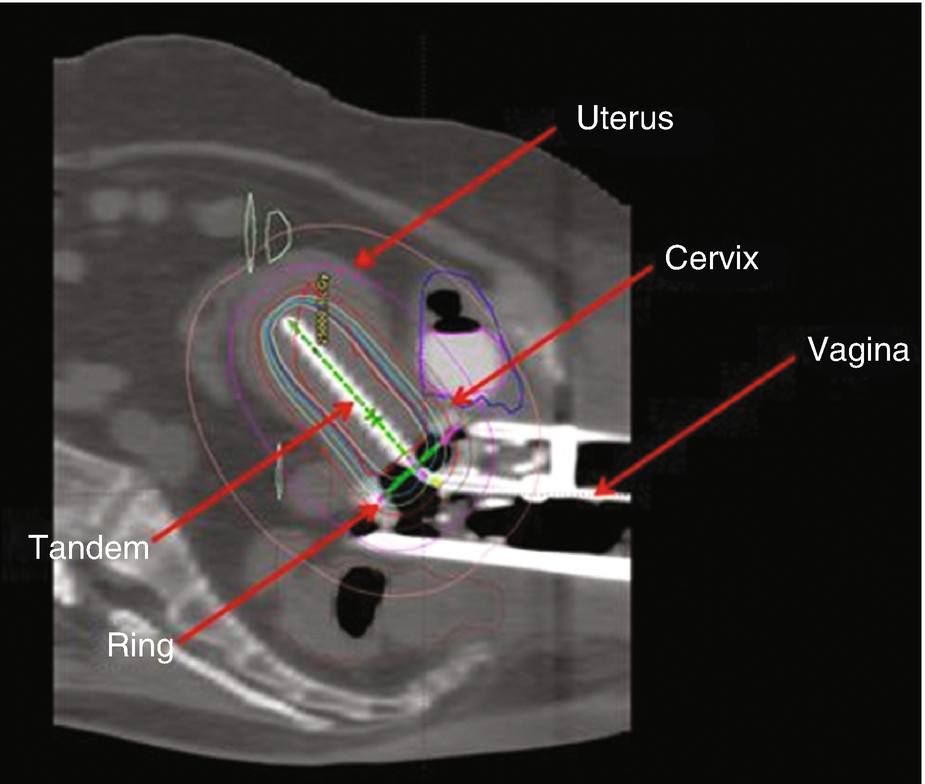

Intracavitary brachytherapy remains the most commonly practiced form of brachytherapy for cervical cancer 30 A wide variety of commercially available applicators exists for intracavitary brachytherapy Two of the most common include variations on the Tandem and Ovoid (T&O) or Tandem and Ring (T&R) design The T&O consists of a tandem, an intrauterine tube placed through the cervix to the level of the uterine fundus, and two ovoids (colpostats) that are placed on either side of the cervix. Gynecologic Brachytherapy The 2 brachytherapy approaches are “Tandem and Ovoid” and “Interstitial” When anesthesia is requested, the anticipation is for a neuraxial anesthetic Tandem and Ovoid Tandem and Ovoid therapy is used for cervical cancer The Tandem is a metal tube and the Ovoid are round applicators that sit near the cervix. From A Practical Manual of Brachytherapy, Pierquin & Marinello, Medical Physics Publishing, Madison WI, 1997 Créteil Mold Applicators Dosimetry • Reference isodose (RD) surface 7mm from surface of mold at level of vaginal sources, 7mm from distal end uterine source d•Calce (o sativer.

Tandem and Ovoid Tandem and Ovoid (T&O) treatments are used to treat the cervix, uterus, and upper 12cm of the vagina Tandem and Ovoid applicators, such as the Fletcher Suite applicator, consist of a central tandem inserted through the cervical os and into the uterus and two ovoids (colpostats) which are placed in the left and right vaginal fornices. Tandem and Ovoid Tandem and Ovoid (T&O) treatments are used to treat the cervix, uterus, and upper 12cm of the vagina Tandem and Ovoid applicators, such as the Fletcher Suite applicator, consist of a central tandem inserted through the cervical os and into the uterus and two ovoids (colpostats) which are placed in the left and right vaginal fornices. Brachytherapy is an international and multidisciplinary journal that publishes original peerreviewed articles and selected reviews on the techniques and clinical applications of interstitial radiation, endovascular brachytherapy, and systemic brachytherapy in the management of cancer and cardiac and other diseases Laboratory and experimental research relevant to clinical practice is also included.

Tandem and Ovoid (T&O) treatments are used to treat the cervix, uterus, and upper 12cm of the vagina Tandem and Ovoid applicators, such as the Fletcher Suite applicator, consist of a central tandem inserted through the cervical os and into the uterus and two ovoids (colpostats) which are placed in the left and right vaginal fornices. Brachytherapy is a method by which a radioactive source is placed in the part of the body that is to be treated and a high dose of radiation is given to a very limited area The advantage of brachytherapy over external beam irradiation is that the dose is concentrated in a small area. High doserate Brachytherapy (HDR) Sometimes called temporary Brachtherapy, is suited for both earlystage and some locallyadvanced prostate cancers (up t o s tage T3b) It is used in conjunction with external beam radiotherapy and/or Hormone treatment In some instances, HDR Brachytherapy may be used as a sole treatment.